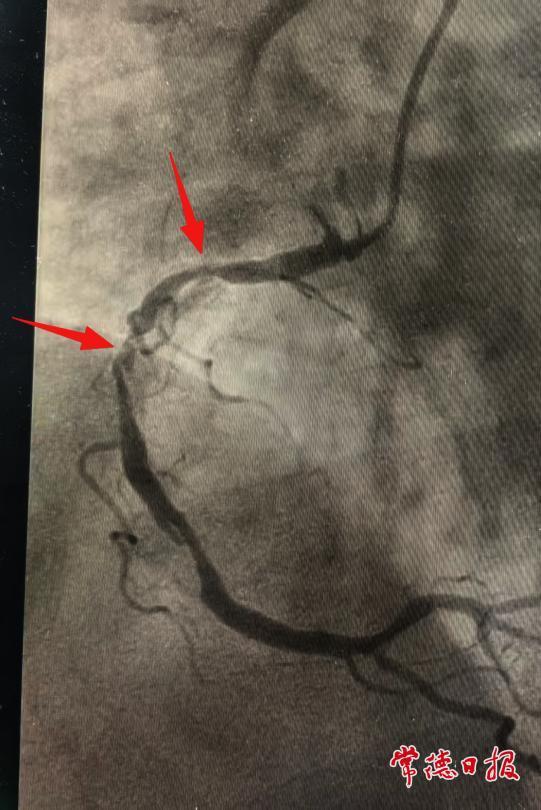

120急救人員到達(dá)現(xiàn)場后,將蘇醒的陳老快速轉(zhuǎn)運(yùn)至常德市第一中醫(yī)醫(yī)院。經(jīng)檢查確診為急性心肌梗死,心血管科二病區(qū)介入團(tuán)隊(duì)立即為其實(shí)施急診介入手術(shù),置入支架2枚,術(shù)后患者病情逐步穩(wěn)定。